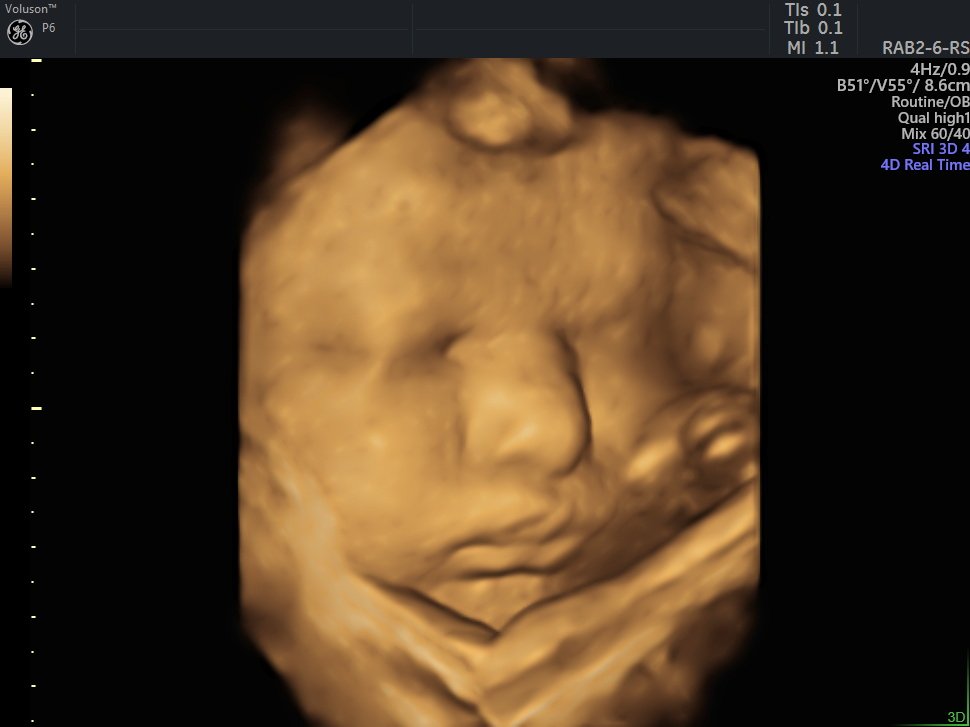

4 D Ultrasonografi

4 Boyutlu (Renkli) Ultrason ve Doppler Ultrasonografi